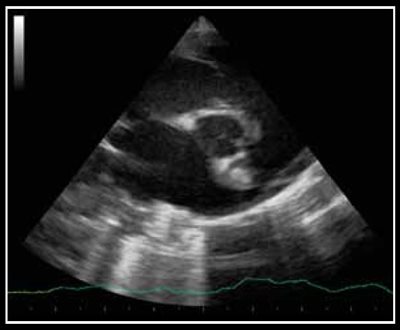

Photo 3 - Persistance du canal artériel, mode bidimensionnel sur une coupe longitudinale des gros vaisseaux par abord parasternal crânial et dorsal gauche.

Le canal artériel est visualisé dans 96 % des cas en mode bidimensionnel ou en mode Doppler couleur sur une coupe petit axe transaortique par abord parasternal droit (Photo 1), sur une coupe petit axe par abord parasternal crânial gauche (Photo 2), ou plus facilement sur une coupe longitudinale des gros vaisseaux (aorte et tronc pulmonaire) par abord parasternal crânial et dorsal gauche (Photo 3).